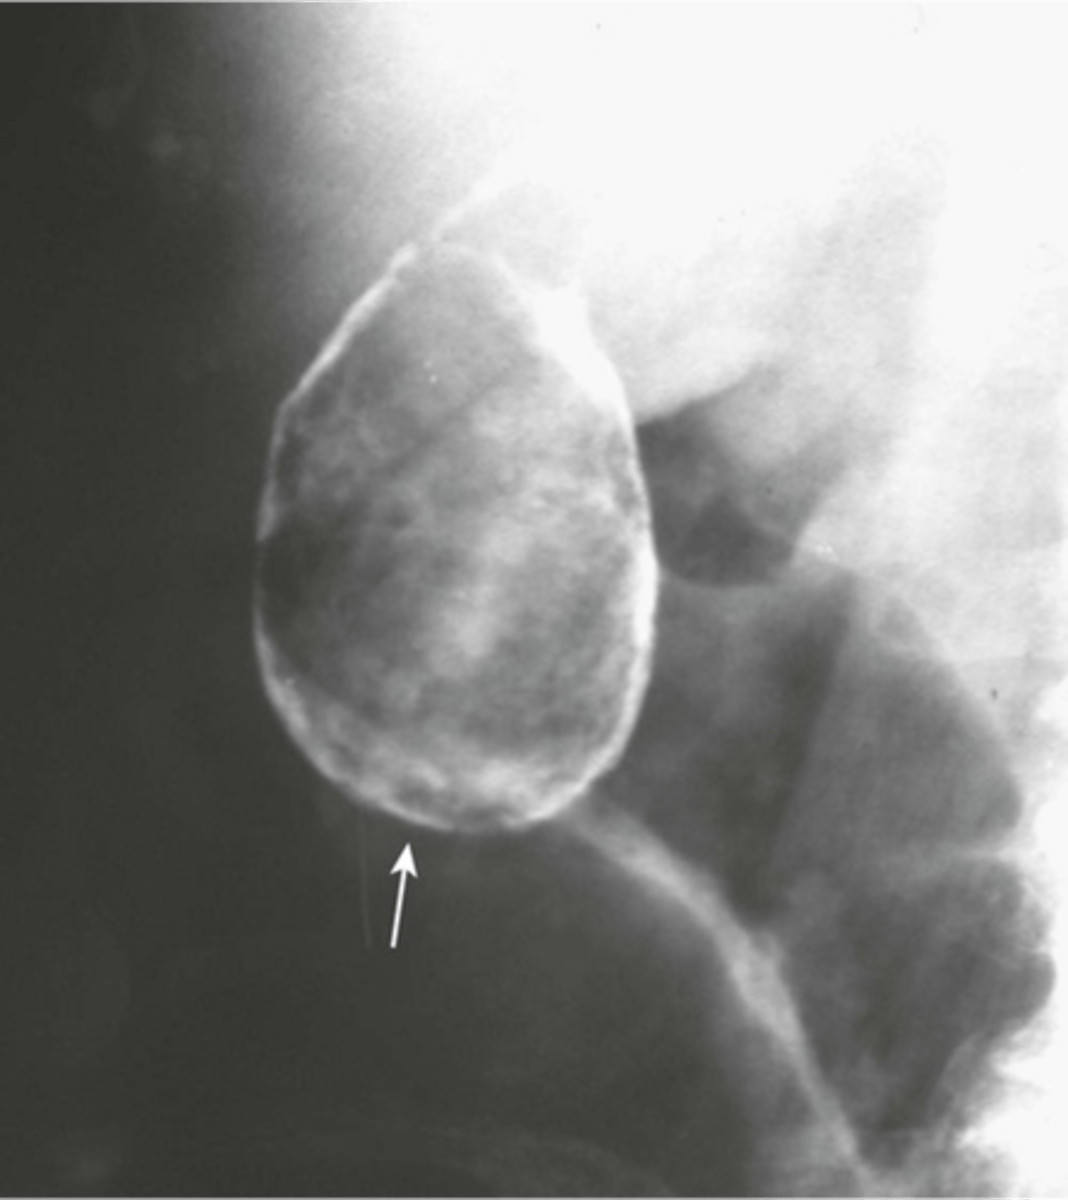

Normal colonic distension (barium enema study)

shows large bowel on barium swallow with follow through